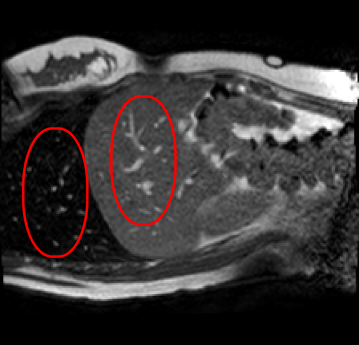

Qualitative results are shown in Fig. 4. We observe no large qualitative differences in the performances of MFIN and MFINc for either loss function. Since, MFINc-SSIM provides the best quantitative results, we show interpolated images from this method and compare them against SCIN-SSIM. Both methods perform well when the motion between the neighbouring images is low. This is reflected in the absence of any structures in the error images in Fig. 4.1. However, RMSE is lower for SCIN because it produces a denoised interpolated image, while MFIN carries over the noise pattern from the neighbouring known image. Whenever there exists high motion between the images being interpolated, SCIN produces blurry images and often misses image structures. This can be observed in cases 2-4 in Fig. 4. For all these cases, MFINc (and also MFIN) produces sharp images and largely preserves structures in the images. Fig. 4.2 shows a case where MFINc additionally has a much better performance with respect to image alignment. Fig. 4.3 shows a representative case, with small improvement in image alignment, yet worse RMSE and SSIM values for MFINc. Finally, Fig. 4.4 shows a case, where MFINc produces worse alignment of structures than SCIN.

Fig. 4 shows a comparison of a representative motion field predicted by MFINc with that computed via the GS registration algorithm. We can see that the motion field produced by MFINc is smooth and has sharper motion boundaries. The reason for this might be that the used registration is more regularized due to its parametric model, where motion is defined by a grid of control points with 4x4 pixel spacing and linearly interpolated in between. This might also explain the higher error in evaluation of the flow field predicted by the network over the whole image (RefMotErrFl) than only over the liver (RefMotErrFlLiver).

a

b

c

d